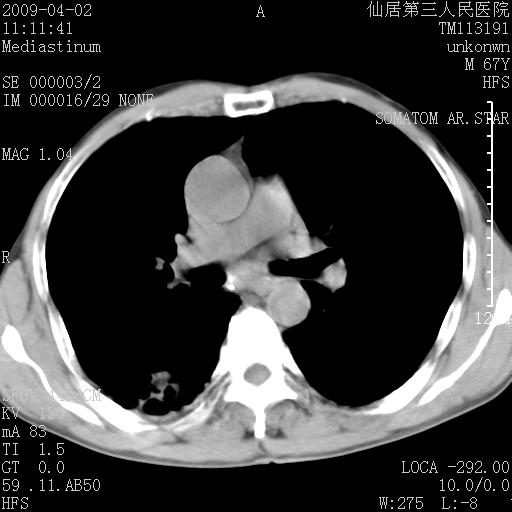

患者老年男性,乏力畏寒来诊,摄胸片示右下肺感染性病变,抗炎两周后复查胸片,无好转有进展。

后做ct平扫表现如下:

考虑右肺炎症可能性大,不除外细支气管肺泡癌

是否还要考虑肺间质纤维化,建议hrct扫描。

考虑间质性肺炎。

病灶呈蜂窝征,纵隔多个淋巴结肿大;肺泡癌需考虑

右肺下叶背段干酪性肺炎。请痰检[emb28]

我认为普通的感染应该可以除外,间质性肺炎可能性较大,但如何解释纵膈的淋巴结肿大呢

考虑双肺间质性改变(间质纤维化?)伴右肺下叶感染。

支持11楼,考虑肺结核.年䶨;大,抗炎无效.纵隔淋巴结肿大.老年人下肺结核要警提